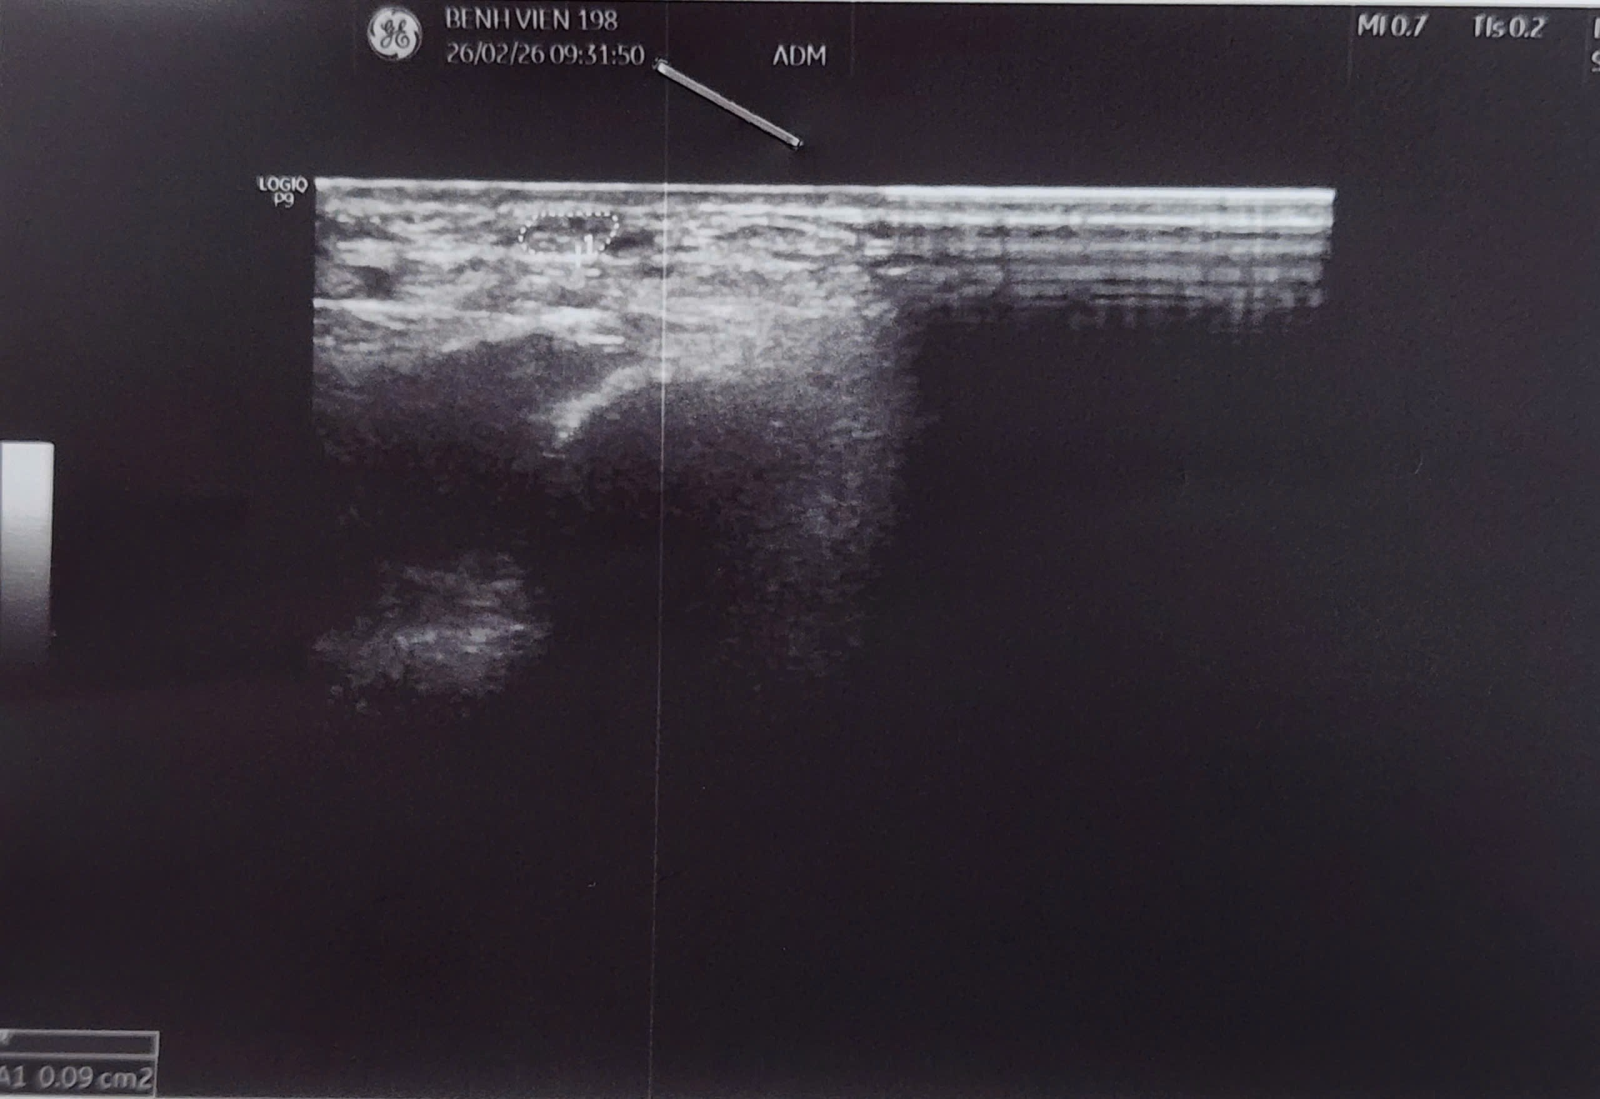

Khi đến khám tại khoa Chấn thương chỉnh hình, phẫu thuật tạo hình và Y học thể thao (CTCH – PTTH & YHTT) – Bệnh viện 19-8, qua thăm khám lâm sàng và được siêu âm thần kinh ghi nhận hình ảnh thần kinh trụ tăng kích thước rõ rệt tại rãnh khuỷu, có dấu hiệu chèn ép. Bện nhân được chẩn đoán: HỘI CHỨNG CHÈN ÉP THẦN KINH TRỤ ĐOẠN KHUỶU (Cubital Tunnel Syndrome).

Hình 2. Siêu âm phát hiện dây thần kinh trụ tăng kích thước

Siêu âm thần kinh: thấy thần kinh trụ dày lên, phù nề